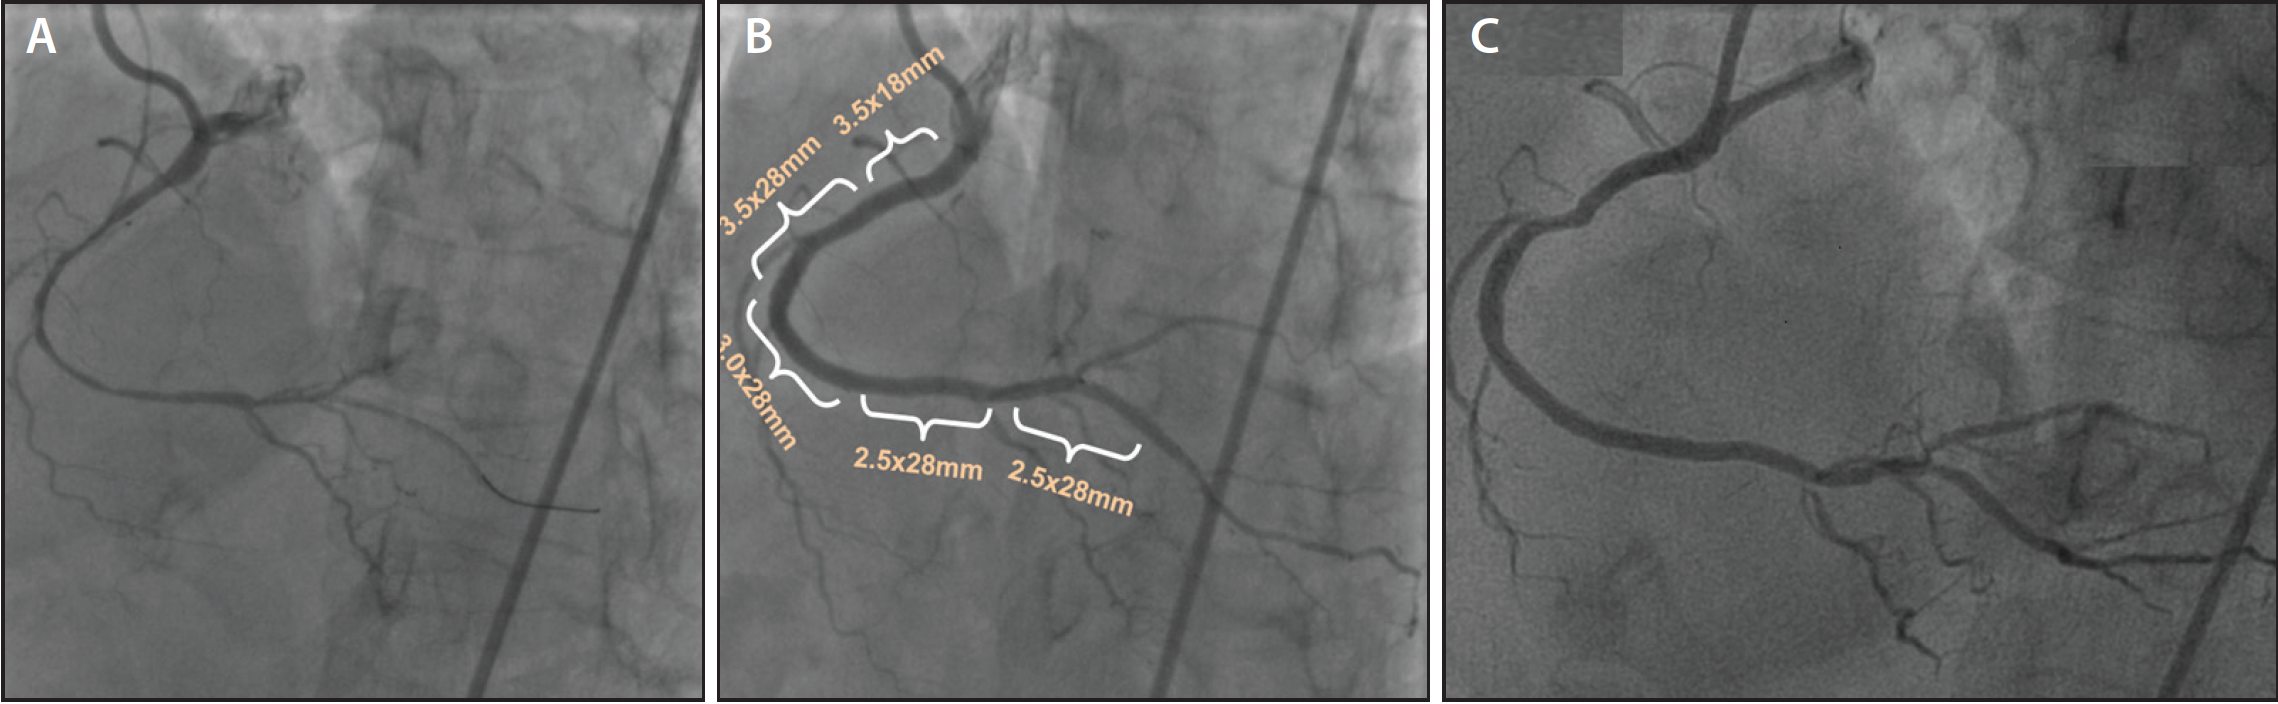

Figure 2. Diffuse right coronary artery disease treated with multiple overlapping scaffolds covering 13 cm of the vessel: diffusely diseased right coronary artery (A); full plastic jacket (five scaffolds) (B); coronary angiography demonstrating the patent right coronary artery at 2-year follow-up (C).